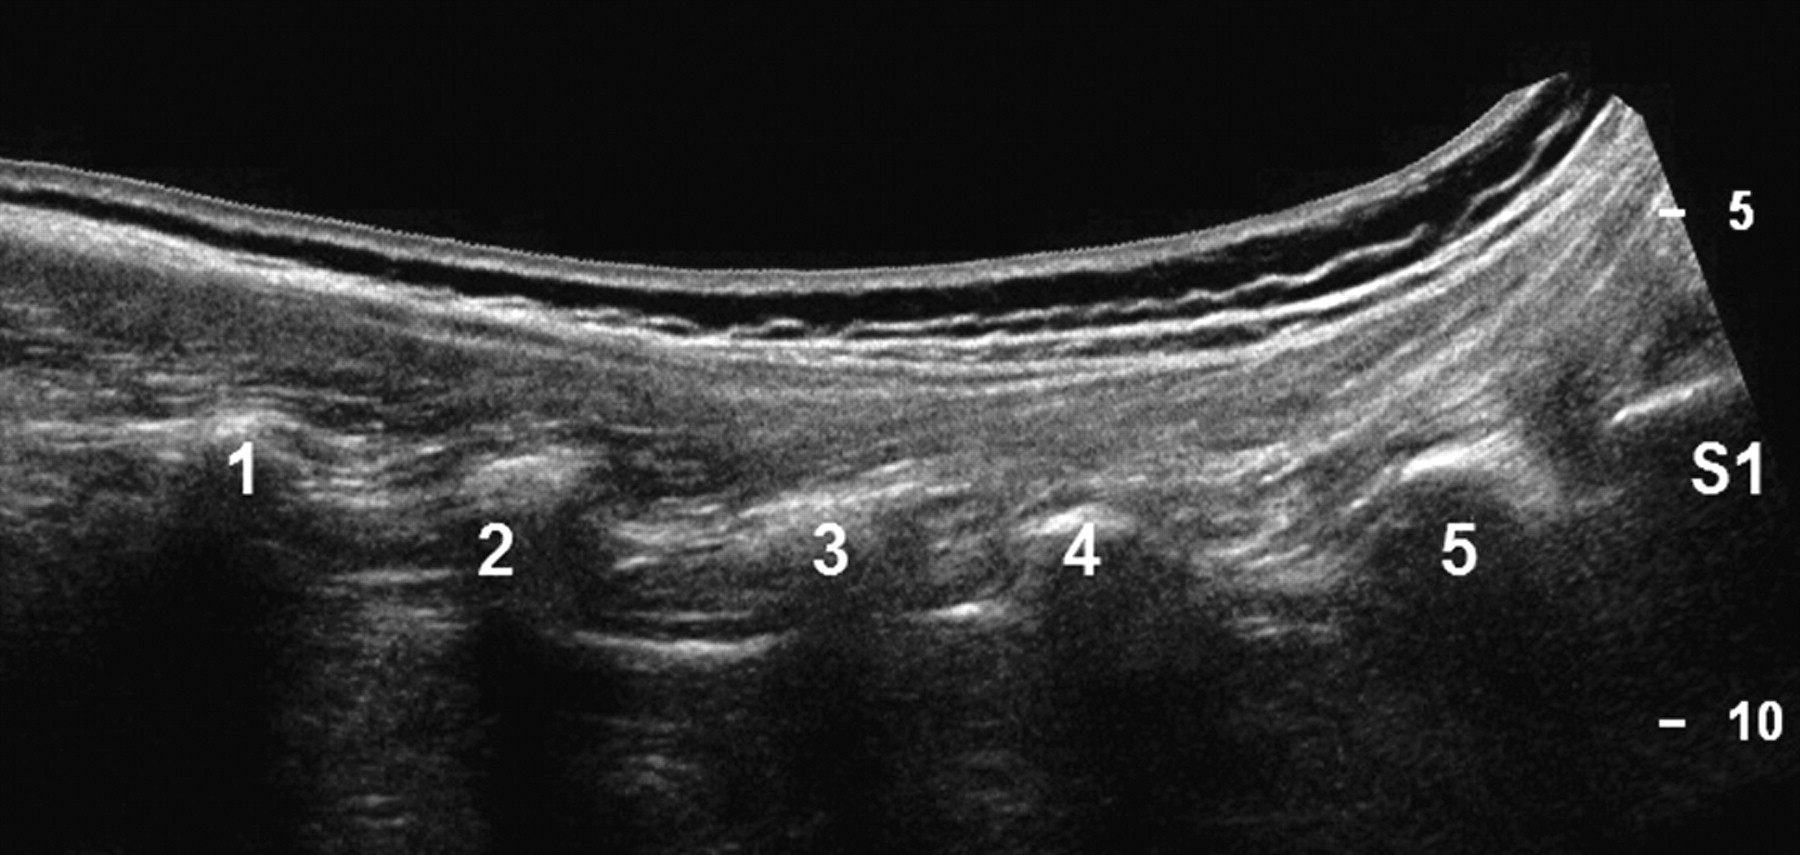

Panoramic (extended FOV) US image of the spinous processes (L1-S1) in a posterior paravertebral parasagittal plane.

Panoramic (extended FOV) US image of the zygapophyseal joints (L1-S1) in a posterior paravertebral parasagittal plane.

Panoramic (extended FOV) US image of the costal processes (L1-S1) in a posterior paravertebral parasagittal plane.